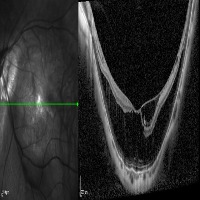

Medical Imaging Analysis: The "three-segment" model can be used by healthcare professionals for enhanced analysis of medical imaging, such as MRI or CT scans. It will help in identifying cleave classes, which can improve detection and diagnosis of potential issues in the brain, particularly those related to retina or neural connections.

Retinal Disease Diagnosis: Ophthalmologists could utilize the model to get help in diagnosing retinal diseases. It can help to identify any abnormalities by differentiating between the 'out', 'in', and 'retina' segments, enabling early detection of conditions such as retinal detachments or macular degeneration.

AI in Surgery: The model can be used to assist surgeons during complex neuro or eye surgeries. It can provide enhanced visualization, enabling real-time differentiation between various segments, leading to more precision in surgical procedures.

Medical Training and Education: The model can be used in medical learning settings, providing students with valuable visual learning material. It could serve as an advanced tool for the understanding of the retina and other segments of the brain or eye.